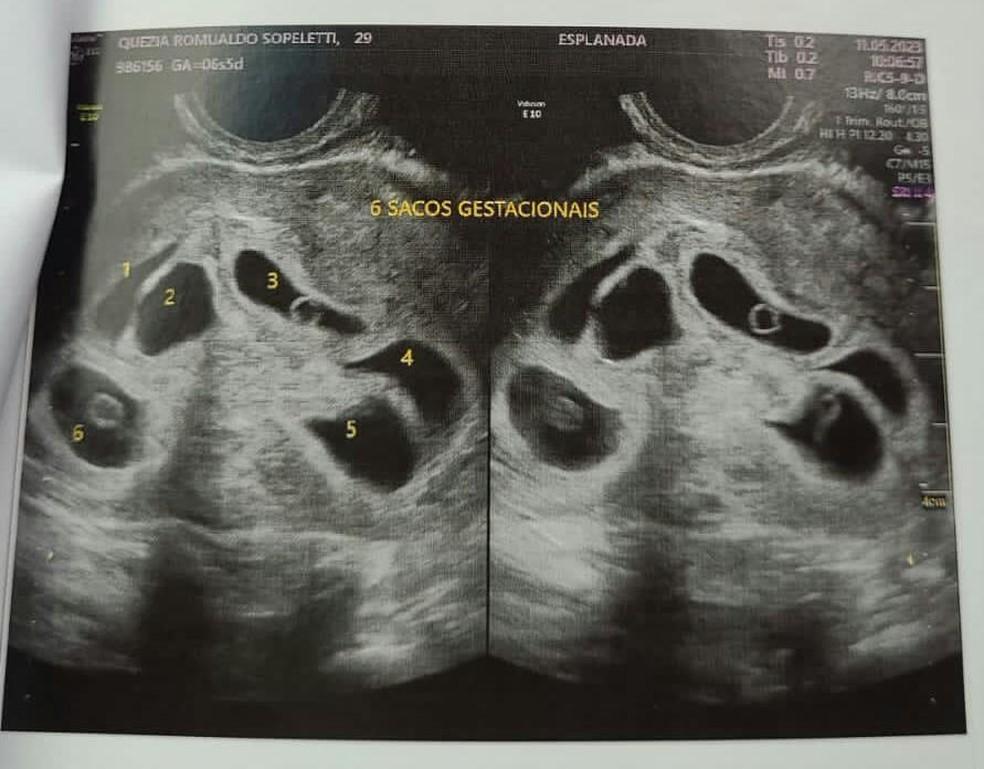

Quezia Romualdo é moradora de Colatina, no Noroeste do Espírito Santo, e descobriu que está grávida de seis filhos dois dias antes do Dia das Mães. A gravidez aconteceu de forma natural

Dois dias antes do Dia das Mães deste ano, Quezia Romualdo, de 29 anos, foi ao médico fazer o primeiro ultrassom de sua segunda gestação. O objetivo era saber se estava correndo tudo bem com a gravidez. Mas a empolgação logo se transformou em surpresa quando, durante o exame, a médica foi mostrando que, na verdade, não era apenas um bebê que Quezia carregava no útero. A médica começou a contar. Primeiro, perceberam que eram três bebês. Depois, a contagem só foi aumentando: 4, 5, até chegar a 6!

Em entrevista ao g1, a radiologista Andréa Raposo, que fez a ultrassom em Quezia na quinta-feira (11), confirmou a gravidez dos sêxtuplos.

Mãe descobre que está grávida de sêxtuplos, em Colatina, no ESUltrassom de Quezia que mostra os seis bebês – Foto: Reprodução/Acervo pessoal